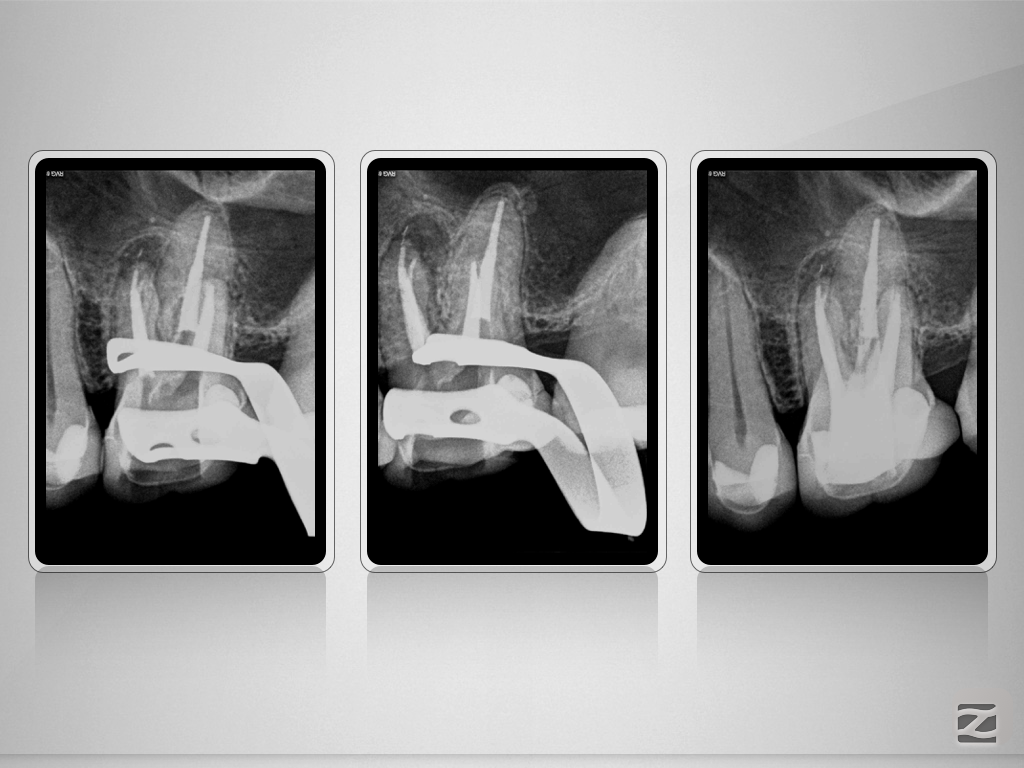

26D.015

X-Bein